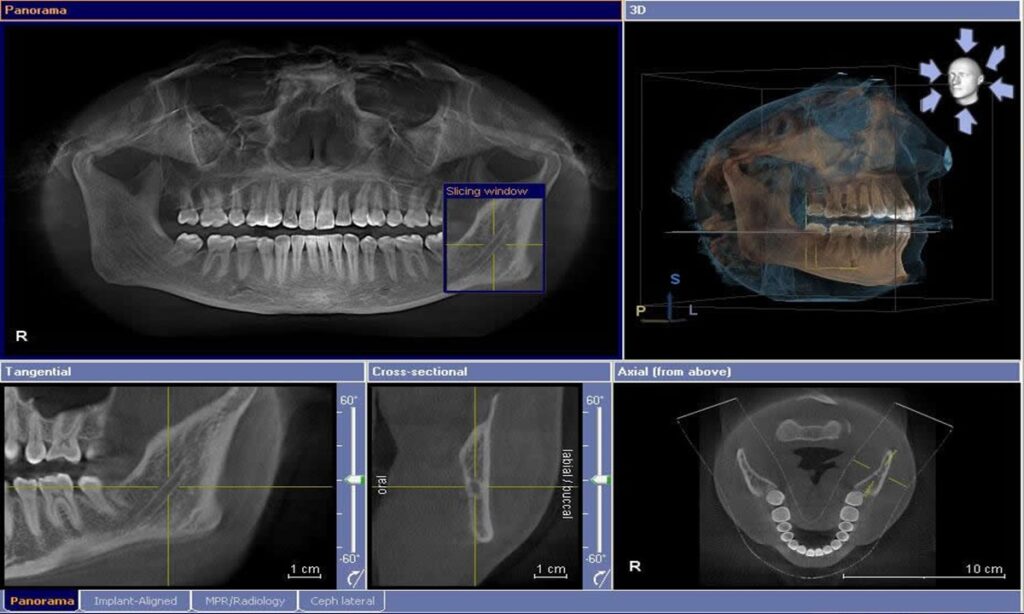

عکس پانورامیک (Panoramic)

پانورامیک یک تصویر کلی از دهان، شامل تمام دندان ها، استخوان های فک و سینوس ها را نشان می دهد. این نوع رادیوگرافی برای تشخیص مشکلات گسترده تر مانند رشد دندان های عقل، مشکلات فک و بررسی وضعیت عمومی دهان و دندان ها به کار می رود.

سی تی اسکن دندان (Dental CT Scan)

سی تی اسکن دندان تصاویری سه بعدی و بسیار دقیق از ساختار دندان ها و استخوان های فک ارائه می دهد. این نوع تصویر برای برنامه ریزی جراحی های مشکل، ایمپلنت های دندانی و بررسی دقیق ناهنجاری های فکی استفاده می شود.